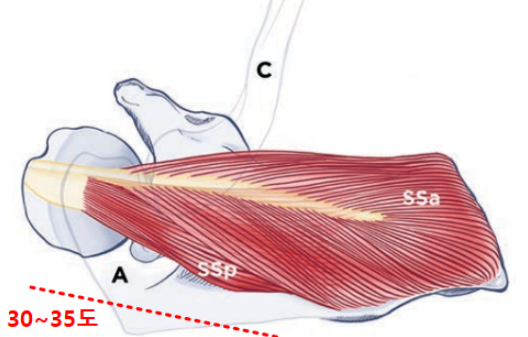

견갑골의 각도는 몸의 중심선(Coronal plane=frontal plane)으로부터 30 ~ 35도 기울어져 있고, 늑골에 거의 바짝 붙어있는것이 정상입니다.

일반적으로 팔을 벌리는(팔벌려 뛰기 동작) 외전과 다르게 견갑골 관절면(Scapular plane)을 따라서 팔을 들어올리는 것을 스캡션(Scaption) 이라고 하는데요.

스캡션(Scaption)시에는 해부적구조상 극상근의 결의 방향과 힘의 방향이 그대로 일치합니다. 따라서 초음파로 동적 검사(Dynamic test) 시 극상근의 파열을 더 잘보려고 할 때 스캡션(Scaption)을 하라고 하면서 저항을 주면서(Full can test와 동일) 극상근의 파열부가 벌어지는것을 초음파로 확인해줄 때 사용합니다.